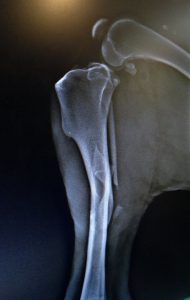

Güneşten saklanmak için yattığı arabanın altından maalesef onu görmeyen sürücü tarafından ezilmiş olarak çıkan köpeğimizin sağ arka bacağında kırık olduğu açıkça görülüyordu.